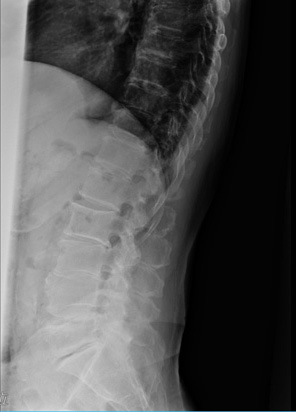

レントゲンで見る背骨の変化

腰痛の原因を調べる際には、単純レントゲン検査が行われることがあります。レントゲンでは骨の形や並び方を確認することができ、背骨の状態を客観的に見ることができます。

例えば、次のような変化が確認されることがあります。

レントゲン検査は短時間で行うことができ、腰痛の原因を探るための大切な手がかりとなります。ただし、腰痛の原因は筋肉や神経など骨以外にある場合もあるため、症状に応じて他の検査が行われることもあります。

腰痛の背景には、日常の姿勢や生活習慣が関係していることがあります。レントゲン検査では、背骨の並びや椎体の状態を確認することができ、腰痛の原因を調べる大切な手がかりになります。日頃から姿勢を意識し、適度な運動や休憩を取り入れながら、腰への負担を減らす生活を心がけましょう。気になる症状がある場合は早めに医療機関へご相談ください。